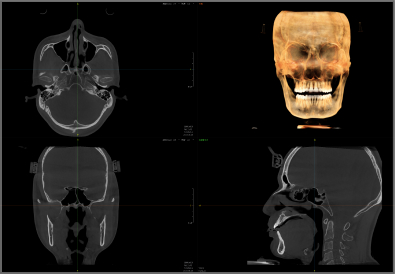

Pirox-A采用多射源并行扫描技术,360°扫描一圈,即可实现非拼接超大视野成像。

实现3D“一成三”成像

单圈扫描可同时获得CT、3D全景及3D正侧位影像,患者无需多次摆位。